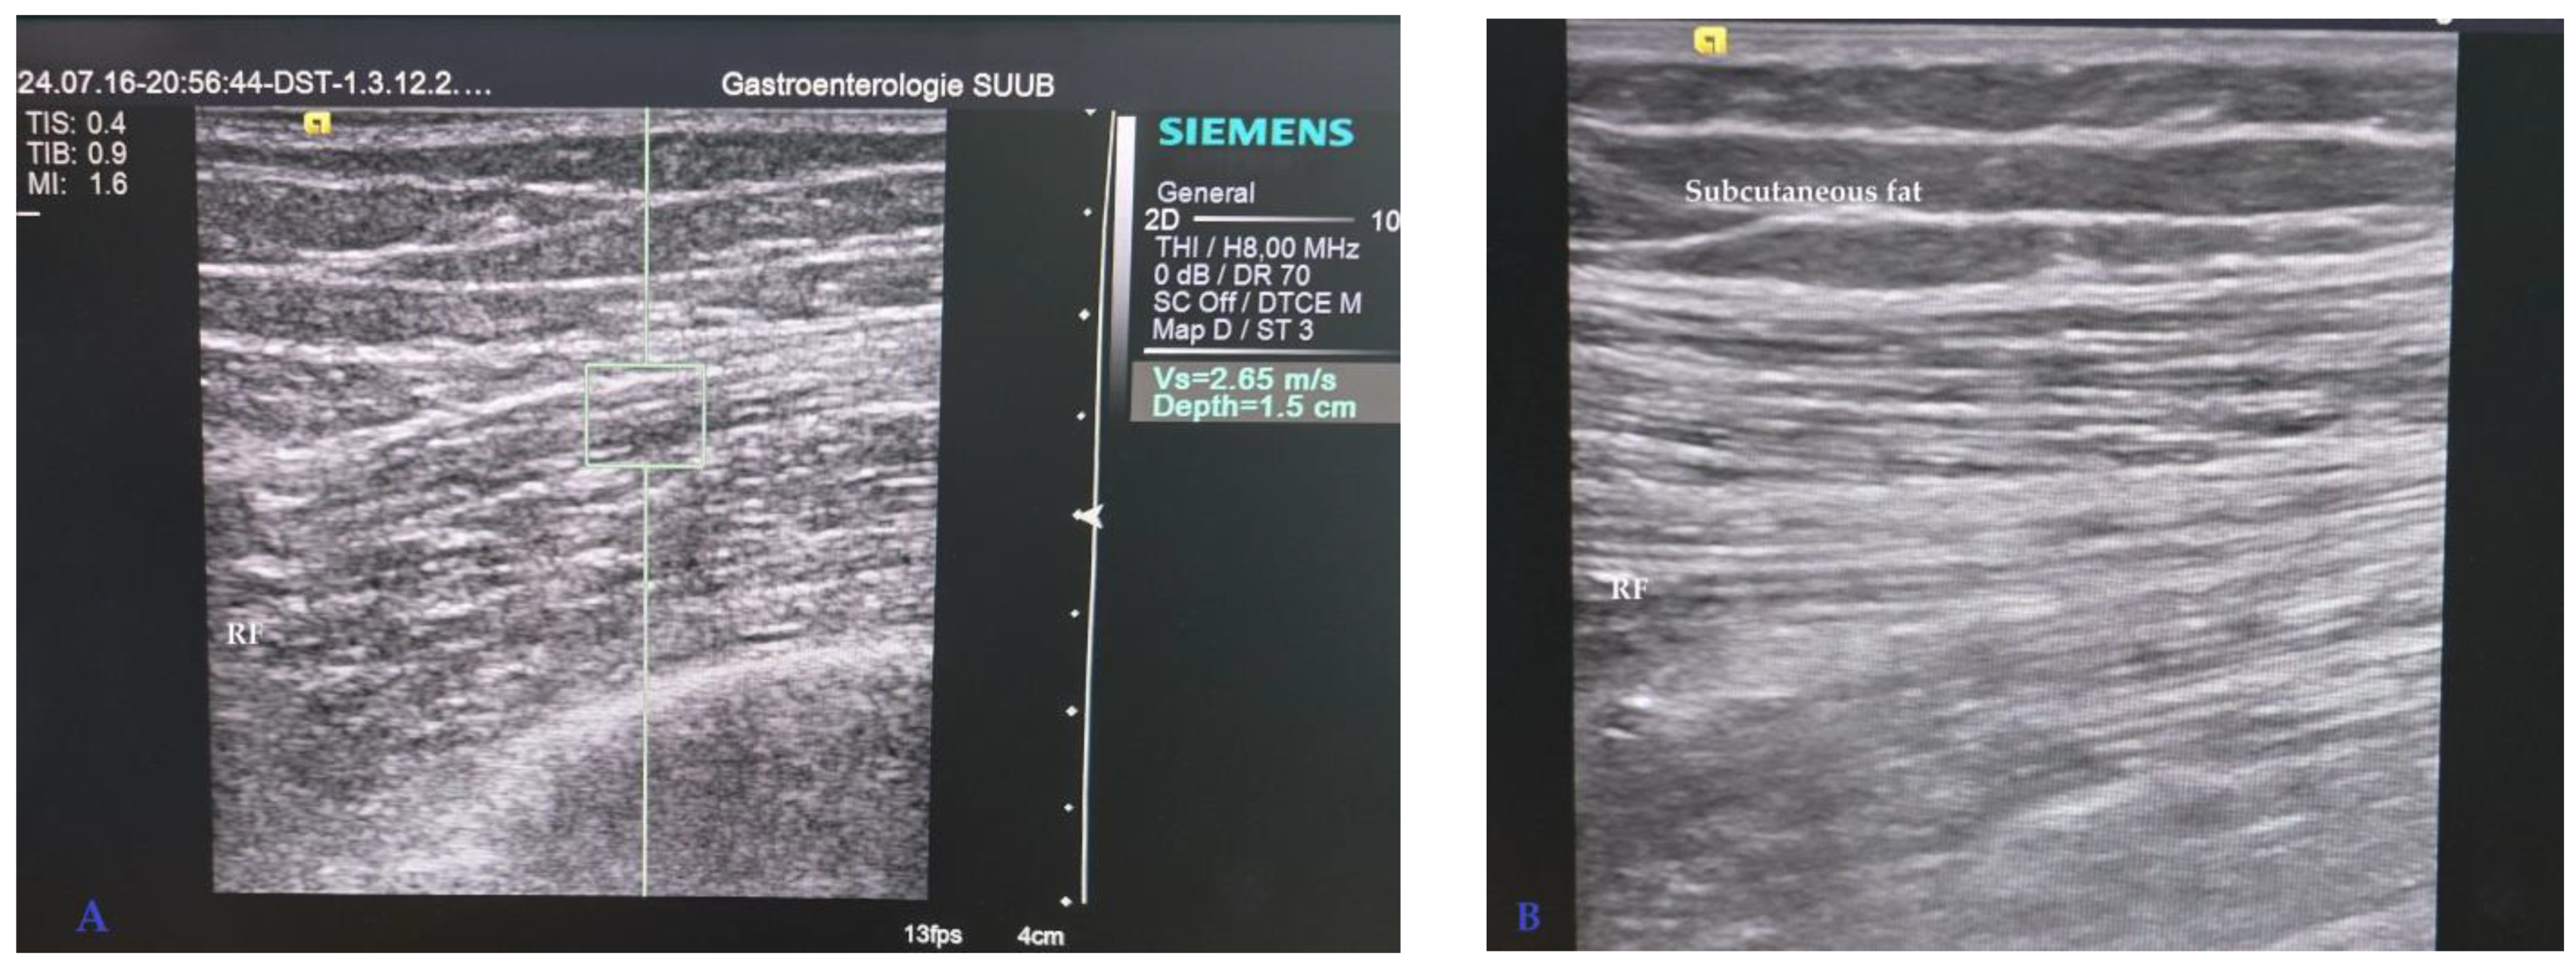

2.2. Ultrasound Assessment of Rectus Femoris

3.3. Rectus Femoris Ultrasound Measurement Results